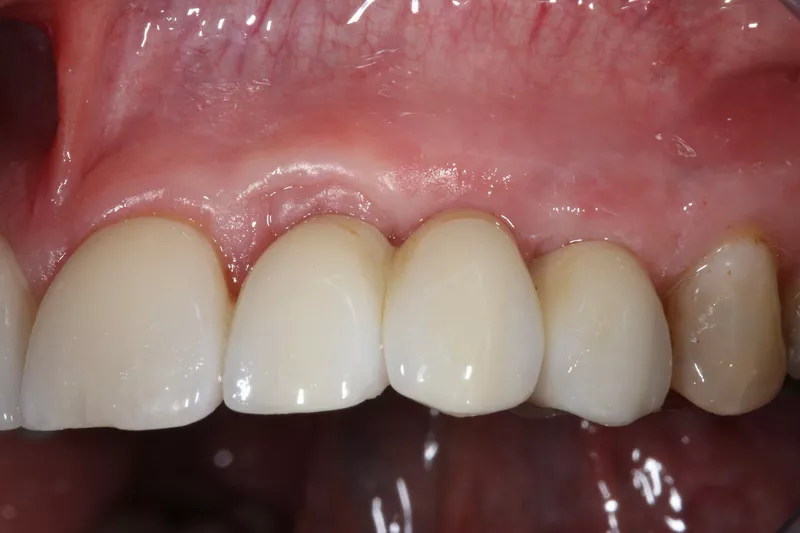

12. State of the soft tissues 8 months after insertion of the implants and 6 months after wearing bridges. Soft tissue volume was satisfactory. A crown was fitted to tooth 15.

13.a-b. Although the soft tissue was healthy, the emergence profile was guided by the resin of the temporary crowns. This material is not ideal, even after polishing.

16a-b. Final situation after inserting bridges to 15 Ncm, cementing the crown to tooth 15, and gluing the veneers to teeth 11 and 21.

18. Situation 4 years post implant placement.